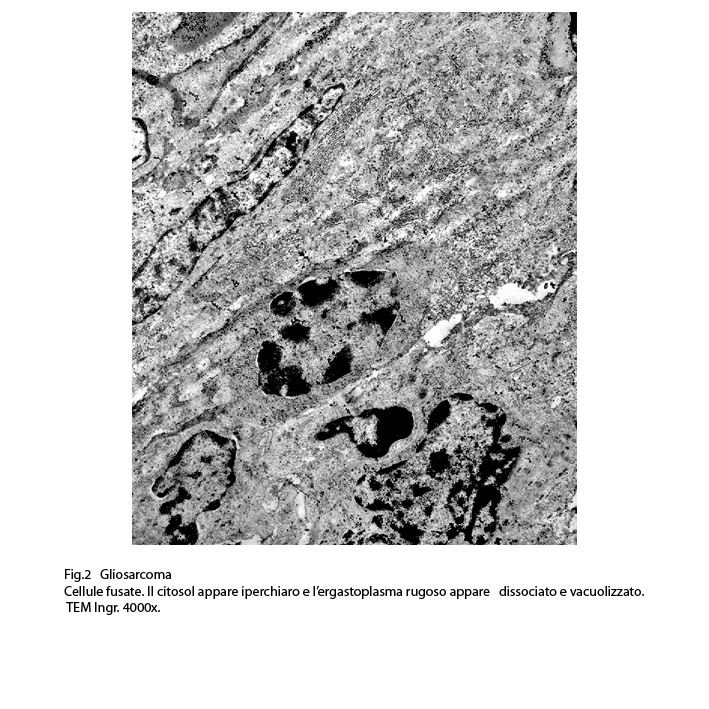

Fig.2  Fig.3

Fig.3